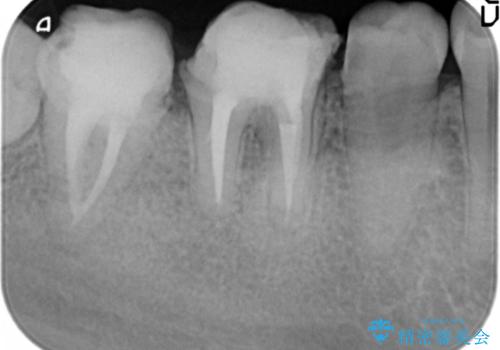

奥歯は既に根管治療が為されクラウンを装着する必要性がある状態ですが、歯の高さが低くクラウンの安定性・強度を担保するために歯周外科を行う治療計画としました。

歯周外科を行うことで、歯ぐきの位置を下げ歯の高さを作り出し安定したクラウンの装着が可能となります。また同時に舌の邪魔となっていた骨隆起の除去を行うこととしました。